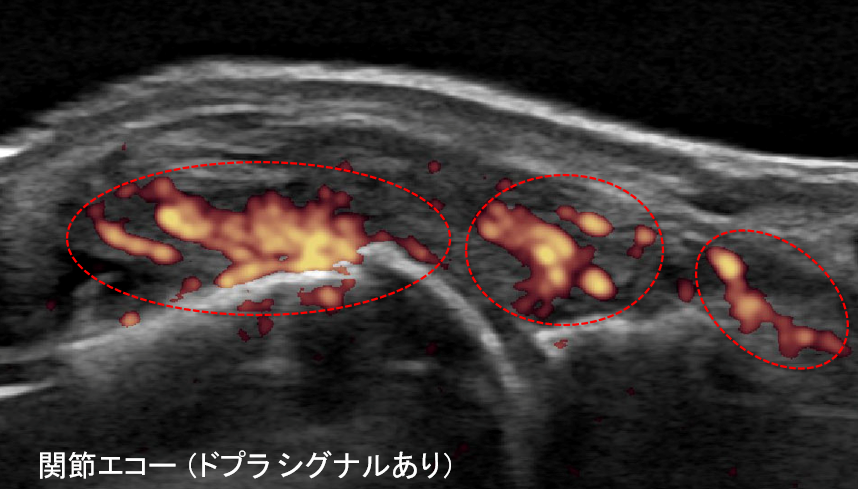

関節エコー検査

関節滑膜の肥厚の有無を判定したり、造影MRI検査より感度は下がりますが、パワードプラ法を用いて血流の増加を確認し、画像的に関節炎の有無を判断できる場合があります。

同一症例における関節造影MRIと関節エコーの比較(滑膜炎あり)

また、骨髄浮腫を捉えることで、将来的な関節破壊のリスクを予測することもできます。関節炎の評価においては、関節造影MRIは関節エコーと比較して、より高感度に病変を検出することが可能です(下の写真)。